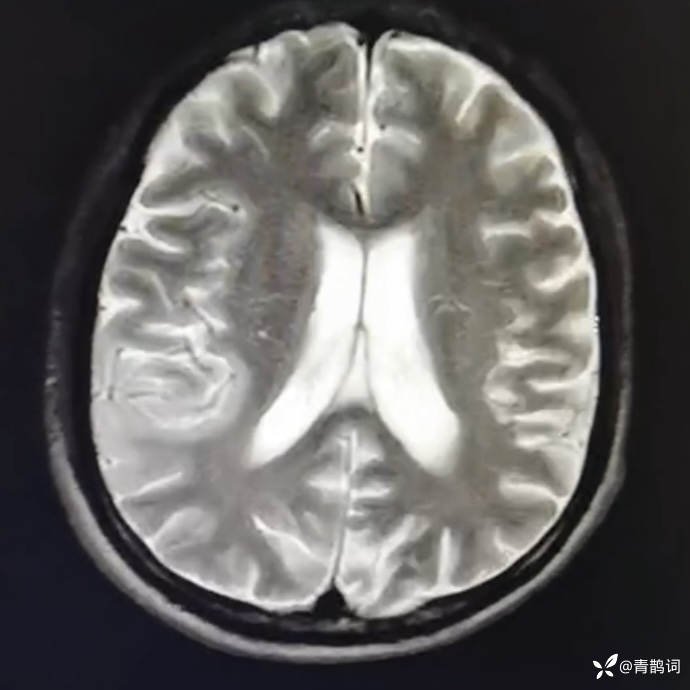

乐痴于医等 2人推荐简要病史:42岁男性,记忆力下降及听力下降一年余。既往体健,否认前驱感染病史。否认家族史。三个月前就诊于当地医院,自述腰穿脑脊液乳酸增高。现就诊于我院,查体记忆力下降,计算力下降,定时定向差,吟诗样语言。完善磁共振如下:

T2: